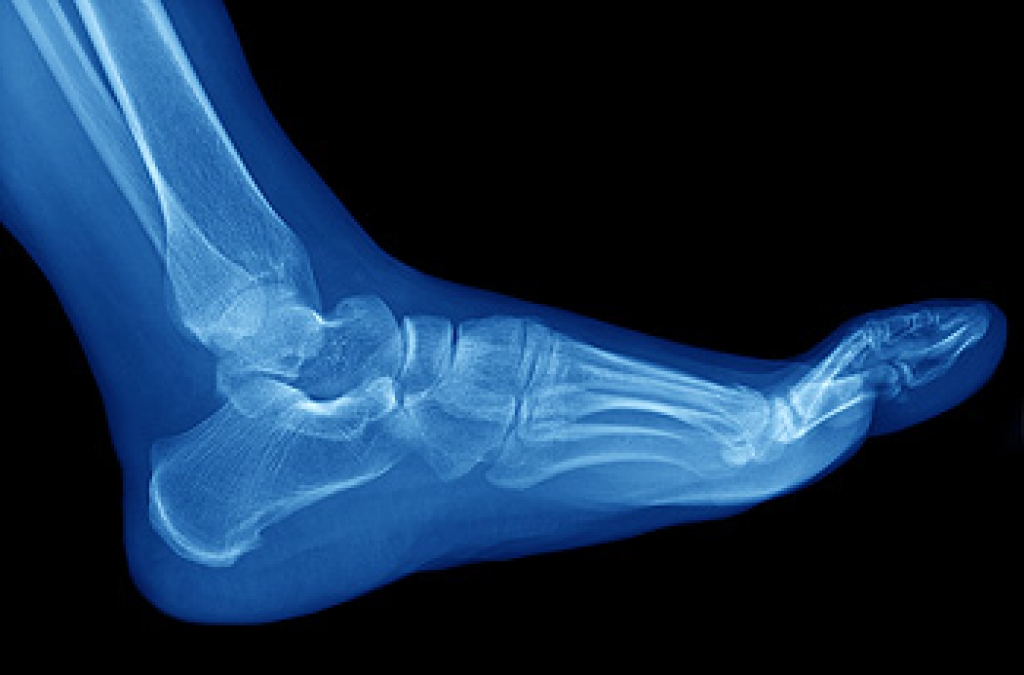

The Achilles tendon is a tendon that connects the lower leg muscles and calf to the heel of the foot. It is the strongest tendon in the human body and is essential for making movement possible. Because this tendon is such an integral part of the body, any injuries to it can create immense difficulties and should immediately be presented to a doctor.

There are various types of injuries that can affect the Achilles tendon. The two most common injuries are Achilles tendinitis and ruptures of the tendon.

Achilles tendon injuries are diagnosed by a thorough physical evaluation, which can include an MRI. Treatment involves rest, physical therapy, and in some cases, surgery. However, various preventative measures can be taken to avoid these injuries, such as: